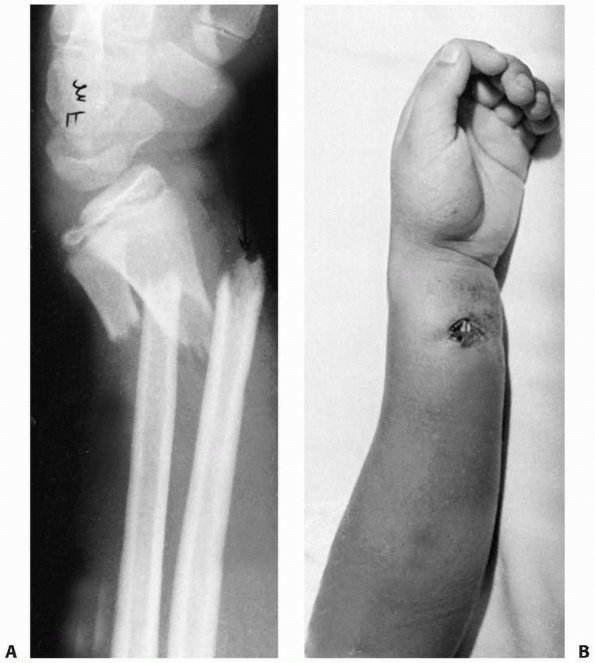

FIGURE 9-22 A.

Ipsilateral distal radial physeal and supracondylar fractures. This 6-year-old sustained both a dorsally displaced distal radial physeal fracture (closed arrow) and a type II displaced supracondylar fracture of the humerus (open arrows). B. Similar case treated with percutaneous pinning of radial physeal fracture and supracondylar humeral fracture. |